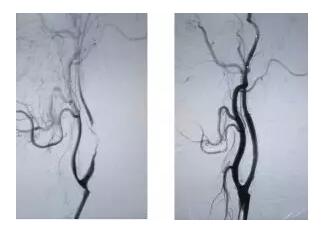

4、部分存在脑血管重度狭窄的患者,经过脑血管病专科医师的系统评估,可以考虑采用(支架)血管成形术或颈动脉内膜剥脱术等预防性手术。必须重点强调的是:(1)支架置入/血管成形术是为了预防脑血管狭窄在将来可能导致的恶性事件(脑梗死),而非治疗性手术,且手术同时还存在小概率的风险,部分风险甚至可能会危及生命;(2)尽管此类手术存在一定风险,但对于绝大部分重度脑血管狭窄的患者而言,此类手术可以有效预防狭窄相关的脑梗死事件。总之,一旦检查发现脑血管狭窄,一定要抱着理性态度与专业的脑血管病医师进行充分沟通,完善相关必要的辅助检查之后再做出最后决定。